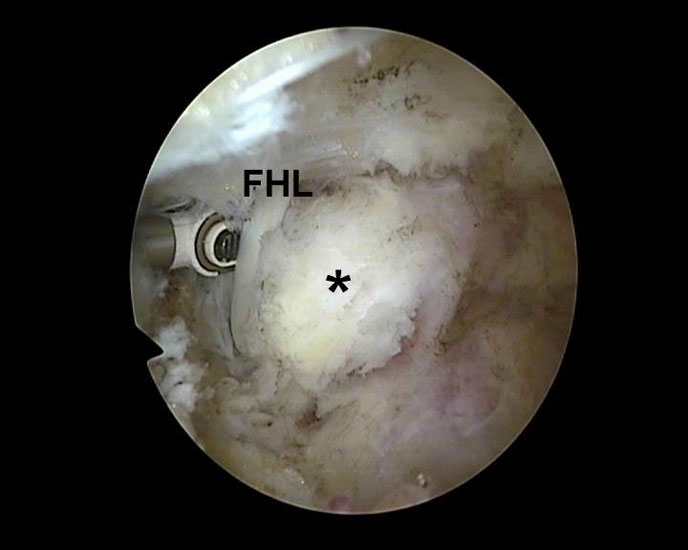

Abbildung Nr. 8-10

Es wird zunächst ein Weichteildebridement durchgeführt, bis die Flexor hallucis longus-Sehne identifiziert werden kann. Während des Debridements sollte auf die korrekte Ausrichtung der Instrumentenöffnung nach lateral geachtet werden. Im Verlauf empfiehlt sich der Wechsel auf eine bipolare Ablationselektrode, die eine gezielte Freilegung der Strukturen unter gleichzeitiger Blutstillung ermöglicht, ohne dabei unkontrolliert Gewebe anzusaugen (rechte Seite, m=medial, l=lateral). Das Os trigonum bzw. die Osteophyten sowie die FHL-Sehne müssen vollständig dargestellt werden (*=Os trigonum, FHL=Flexor hallucis longus-Sehne).